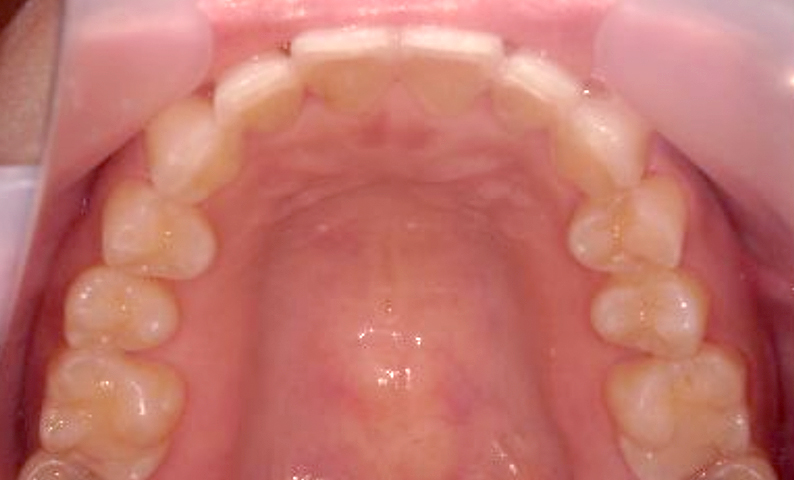

症例_003 下顎だけの部分矯正

治療期間:10ヶ月金額:24万円+税女性前歯のガタガタ下の前歯だけ上顎は補綴治療中